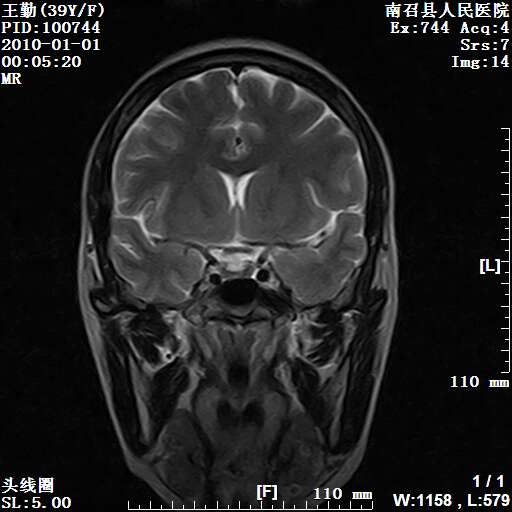

以下是引用随光逐影在2010-1-22 9:03:00的发言:[br]考虑左侧中颅窝(蝶骨翼区)脑膜瘤侵犯蝶骨翼并突入左侧眼眶。

以下是引用水过无痕在2010-1-22 14:55:00的发言:[br]一、定位:颅外占位;二、定性:恶性可能性大;三、组织来源:来源于左侧眼外直肌或其他部位;考虑为:横纹肌肉瘤>转移瘤>脑膜瘤.